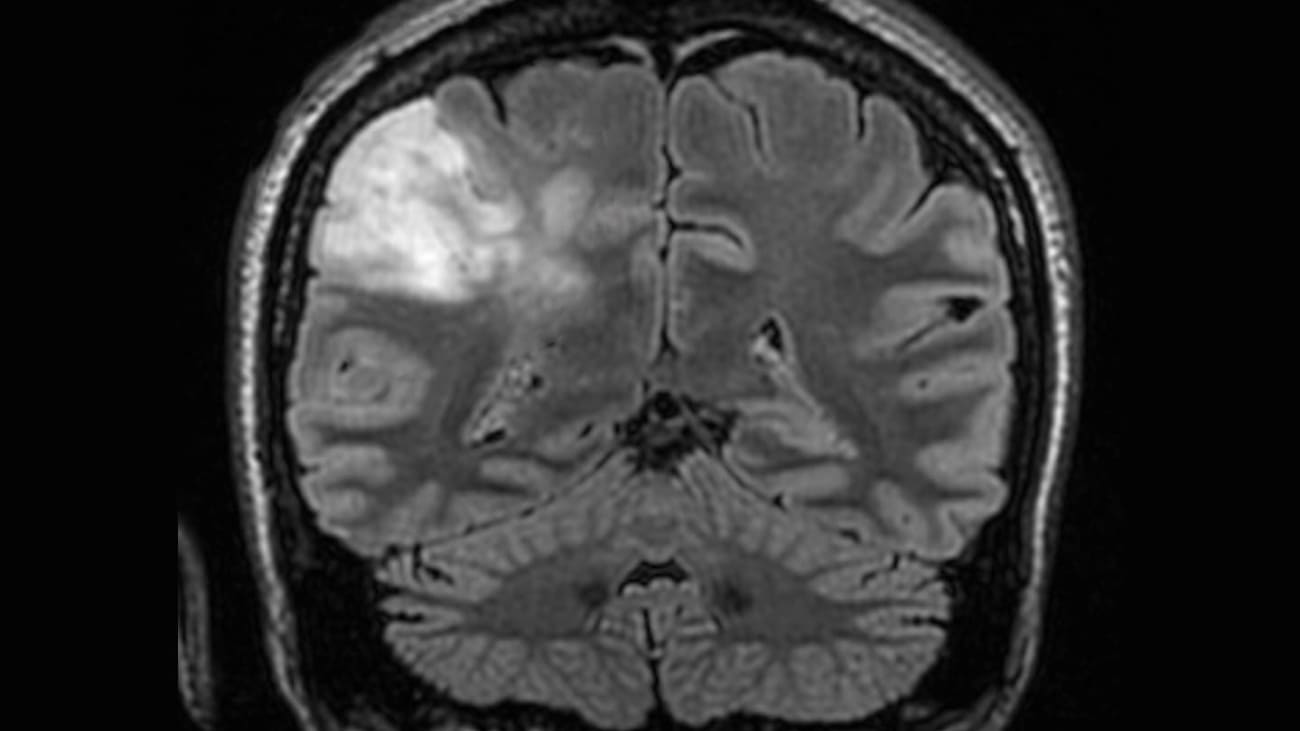

Brain tumour, CT scan Stock Image C026/9955 Science Photo Library Flickering Eyes Brain Tumour Typically, signs and symptoms of a brain tumor include severe headaches, confusion, blurred vision with dizziness and, in some. Headaches and seizures are common brain tumor symptoms. Brain tumour symptoms can include changes in vision, like blurred or double vision, abnormal eye movements, restricted field of. Vision symptoms related to brain tumors may include:. Brain tumors can cause vision changes. Flickering Eyes Brain Tumour.